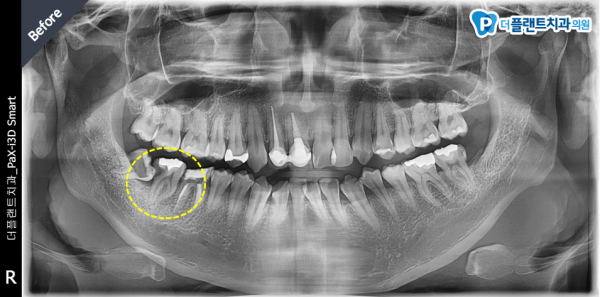

•치료명 : 신경치료

•치료기간 :3주

•치료내용 : #48 매복사랑니 때문에 #47에 심한 충치가 생겨 #47 발치 후

#47 충치로 인한 극심한 통증으로 신경치료 진행하였습니다.

#47 치아의 신경관은 매우 심하게 휘어져 난이도가 상당히 높은 신경치료가 예상 되었지만

다행히 여러 번의 신경치료로 신경치료가 잘 마무리 되었습니다.

환자분 통증도 사라져 정말 다행입니다.